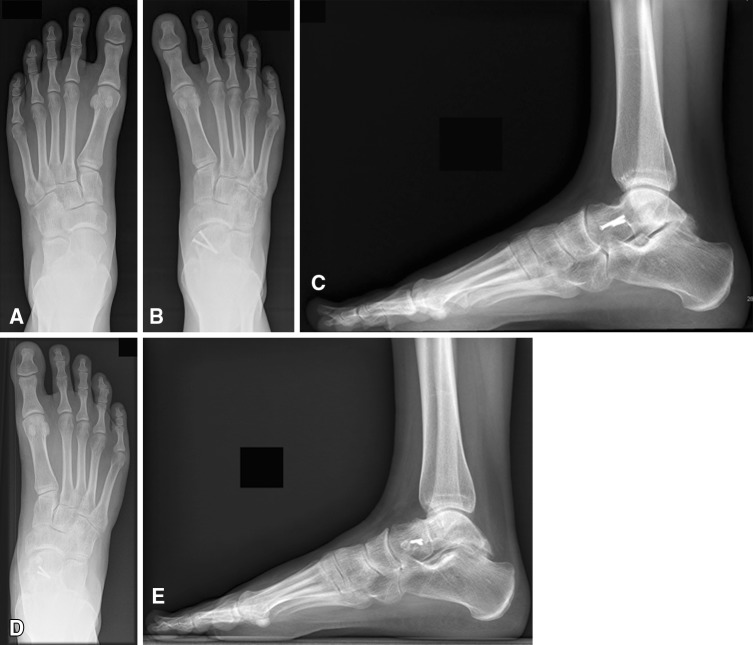

Fig. 4A–E.

(A) An AP radiograph shows the left foot and preoperative (B) AP and (C) lateral radiographs show the right foot of a 17-year-old girl with a malunited talar neck fracture and consecutive shortening of the medial column with supination and adduction deformities of the forefoot. Postoperative (D) AP and (E) lateral radiographs show the foot after partial removal of the implants with a solid union of the lengthening osteotomy of the talus. Radiographically, there was no loss of correction or development of avascular necrosis observed. The plantigrade position of the forefoot can be seen, and the corrected cyma line, compared with the preoperative situation.

All but one patient showed radiographic evidence of union of the talar osteotomy within 2 to 3 months postoperatively (Fig. 4). There was no loss of correction in any of the patients. Radiographically, no avascular necrosis development was observed after correction. Radiographic evidence of arthritic changes did not progress in any patient. A solid fusion on the site of the arthrodesis was detected in two patients, one patient with an additional subtalar arthrodesis and the other after talonavicular and subtalar arthrodesis. The average TMT-I angle increased from 11.9 ± 7.3 (range, −2 to −24) preoperatively to 0.9 ± 4.7 (range, −6 to 6) postoperatively (Table 4).